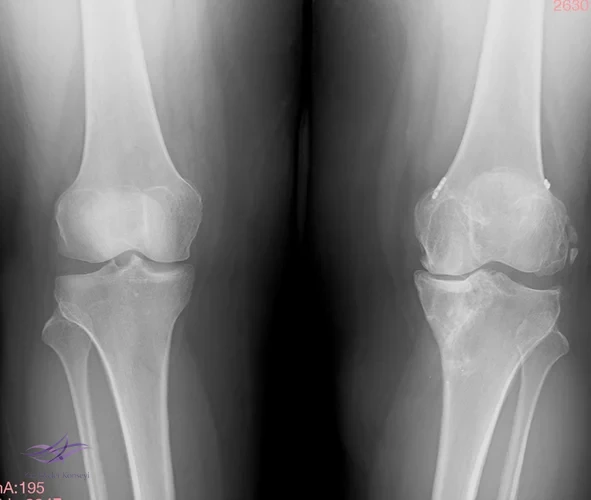

İncelemeler: USG'de minimal suprapatellar efüzyon. MCL heterojen görününde fibrillar yapı bozulmuş. Direkt grafi ve MRG'leri ektedir.

Resim 1. Resim 1. Direkt grafi.